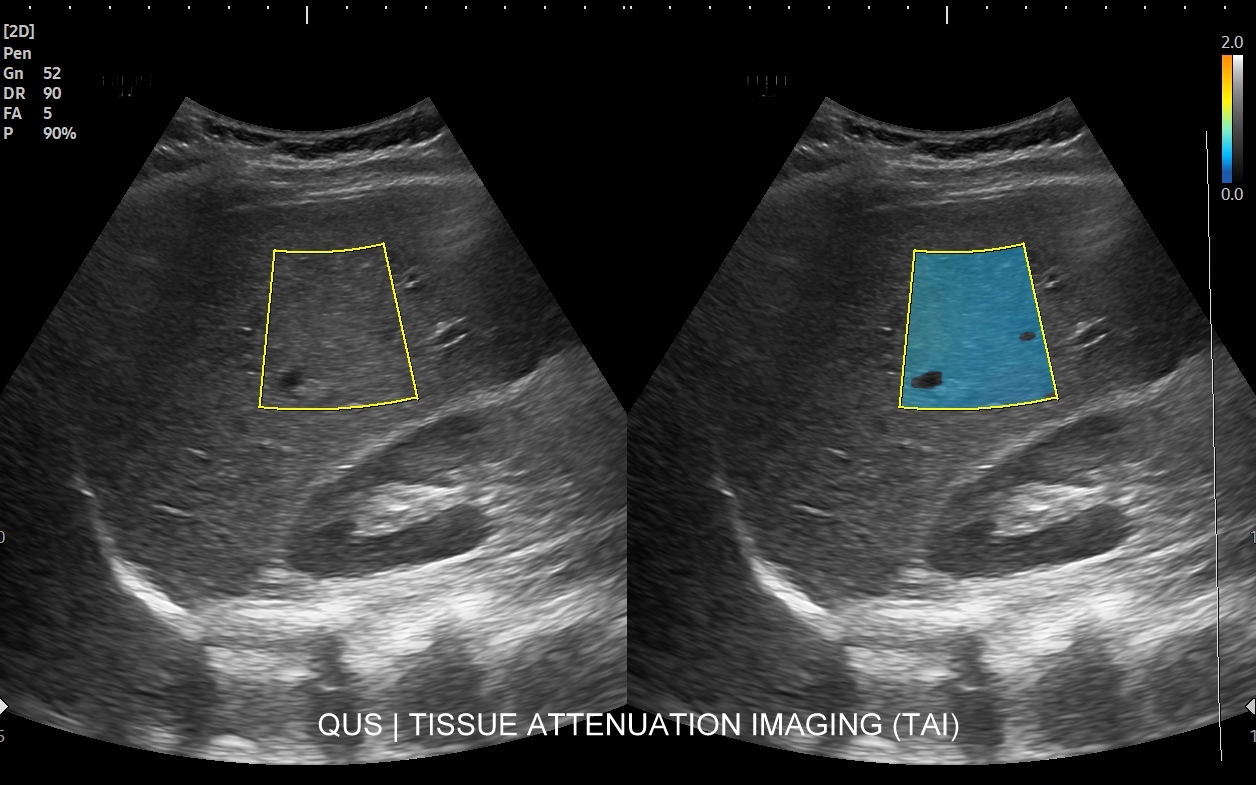

Rozwinięciem standardowego badania USG jamy brzusznej jest badanie multiparametryczne MPUS (ang. multiparametric ultrasound), w ramach którego wykorzystuje się różnorodne, nowoczesne modalności sonograficzne, takie jak tryby mikrounaczynienia MVI, B-flow, elastografię, ilościową ocenę stłuszczenia wątroby QUS, czy tryb Dopplera spektralnego, a to wszystko w celu uzyskania dodatkowej oceny funkcjonalnej i biologicznej struktur, narządów oraz tkanek jamy brzusznej. Obrazowanie MPUS niejednokrotnie poprawia także wizualną ocenę narządów wewnętrznych, czego przykładem jest zastosowanie trybu MVI w ramach bezkontrastowej angiografii sonograficznej naczyń oraz w ocenie guzów nerek. Klasycznymi i najczęstszymi zastosowaniami badania MPUS są jednakże funkcjonalna ocena wątroby w kierunku stłuszczenia, zwłóknienia, zapalenia i nadciśnienia wrotnego, a także ocena żywotności i funkcji nerek.